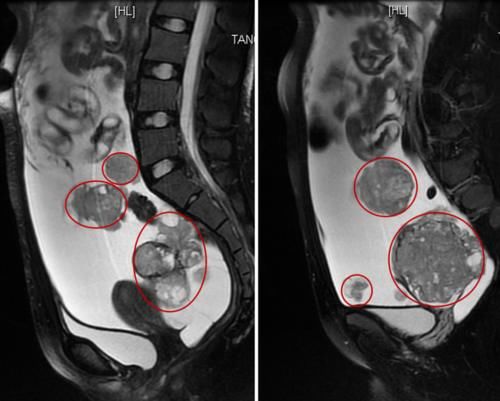

#国民医生说##健闻登顶计划##微博热点优质创作计划# 畸胎瘤是怀了“怪胎”吗?和胚胎发育有关吗?畸胎瘤并不是怀了 “怪胎”,它本质上是一种生殖细胞肿瘤,和正常胚胎发育没有直接关联,这是一个极易引发误解的医学概念。从病理本质来看,畸胎瘤是由胚胎时期的生殖细胞异常分化形成的肿瘤,而非真正的 “胎儿”。生殖细胞本应分化为人体的各类组织器官,但在发育过程中,部分细胞脱离了正常的分化轨道,在卵巢、睾丸等部位异常增殖,最终形成包含多种组织成分的肿瘤 —— 它可能含有毛发、牙齿、骨骼、油脂甚至少量神经组织,这些只是分化紊乱的人体组织,并非完整的胚胎或 “怪胎”。关于和胚胎发育的关联,需要区分两个层面:一方面,畸胎瘤的起源确实和胚胎阶段的生殖细胞有关,其发病根源是胚胎期生殖细胞的分化异常;但另一方面,它和母体的正常妊娠、胚胎孕育没有任何关系,既不是母体怀孕时形成的 “异常胎儿”,也不会因为怀孕而诱发或加重,未婚未育人群也可能患上畸胎瘤。另外,畸胎瘤多数为良性(成熟畸胎瘤),少数为恶性(未成熟畸胎瘤),良性畸胎瘤通过手术切除即可治愈,恶性类型则需结合病理分级进行后续治疗,总体预后相对较好,无需因 “畸胎” 的名称产生过度恐慌。